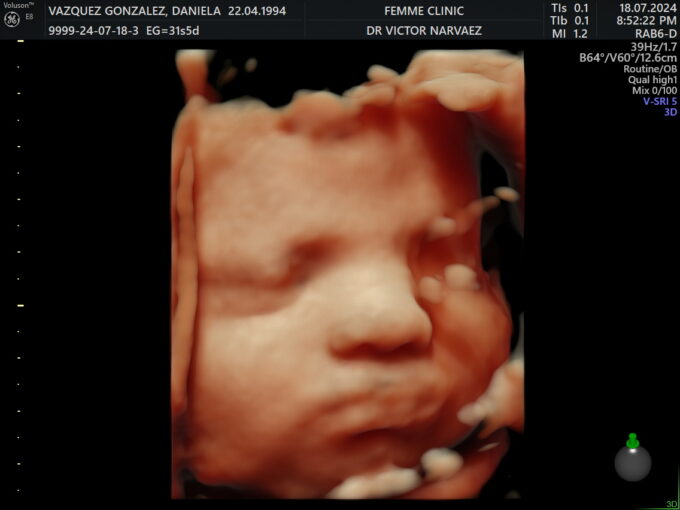

My pregnancy was deeply wanted, carefully cared for, and intentional. I lived each week with respect and attention, knowing that that little heartbeat was the dream of many years. There were moments of fear, like bleeding in the second month, but there was also a very strong certainty: I was doing everything possible to protect that miracle. That’s why I decided to stay quiet almost until the end, protecting that process with all my heart.

Julia Elena was born by C-section, after an intense pregnancy full of emotions. Hearing her cry, seeing her for the first time, and recognizing in her little face something of her dad and something of me was indescribable. Even holding her, kissing her, and looking at her, it was hard to believe she was finally there.